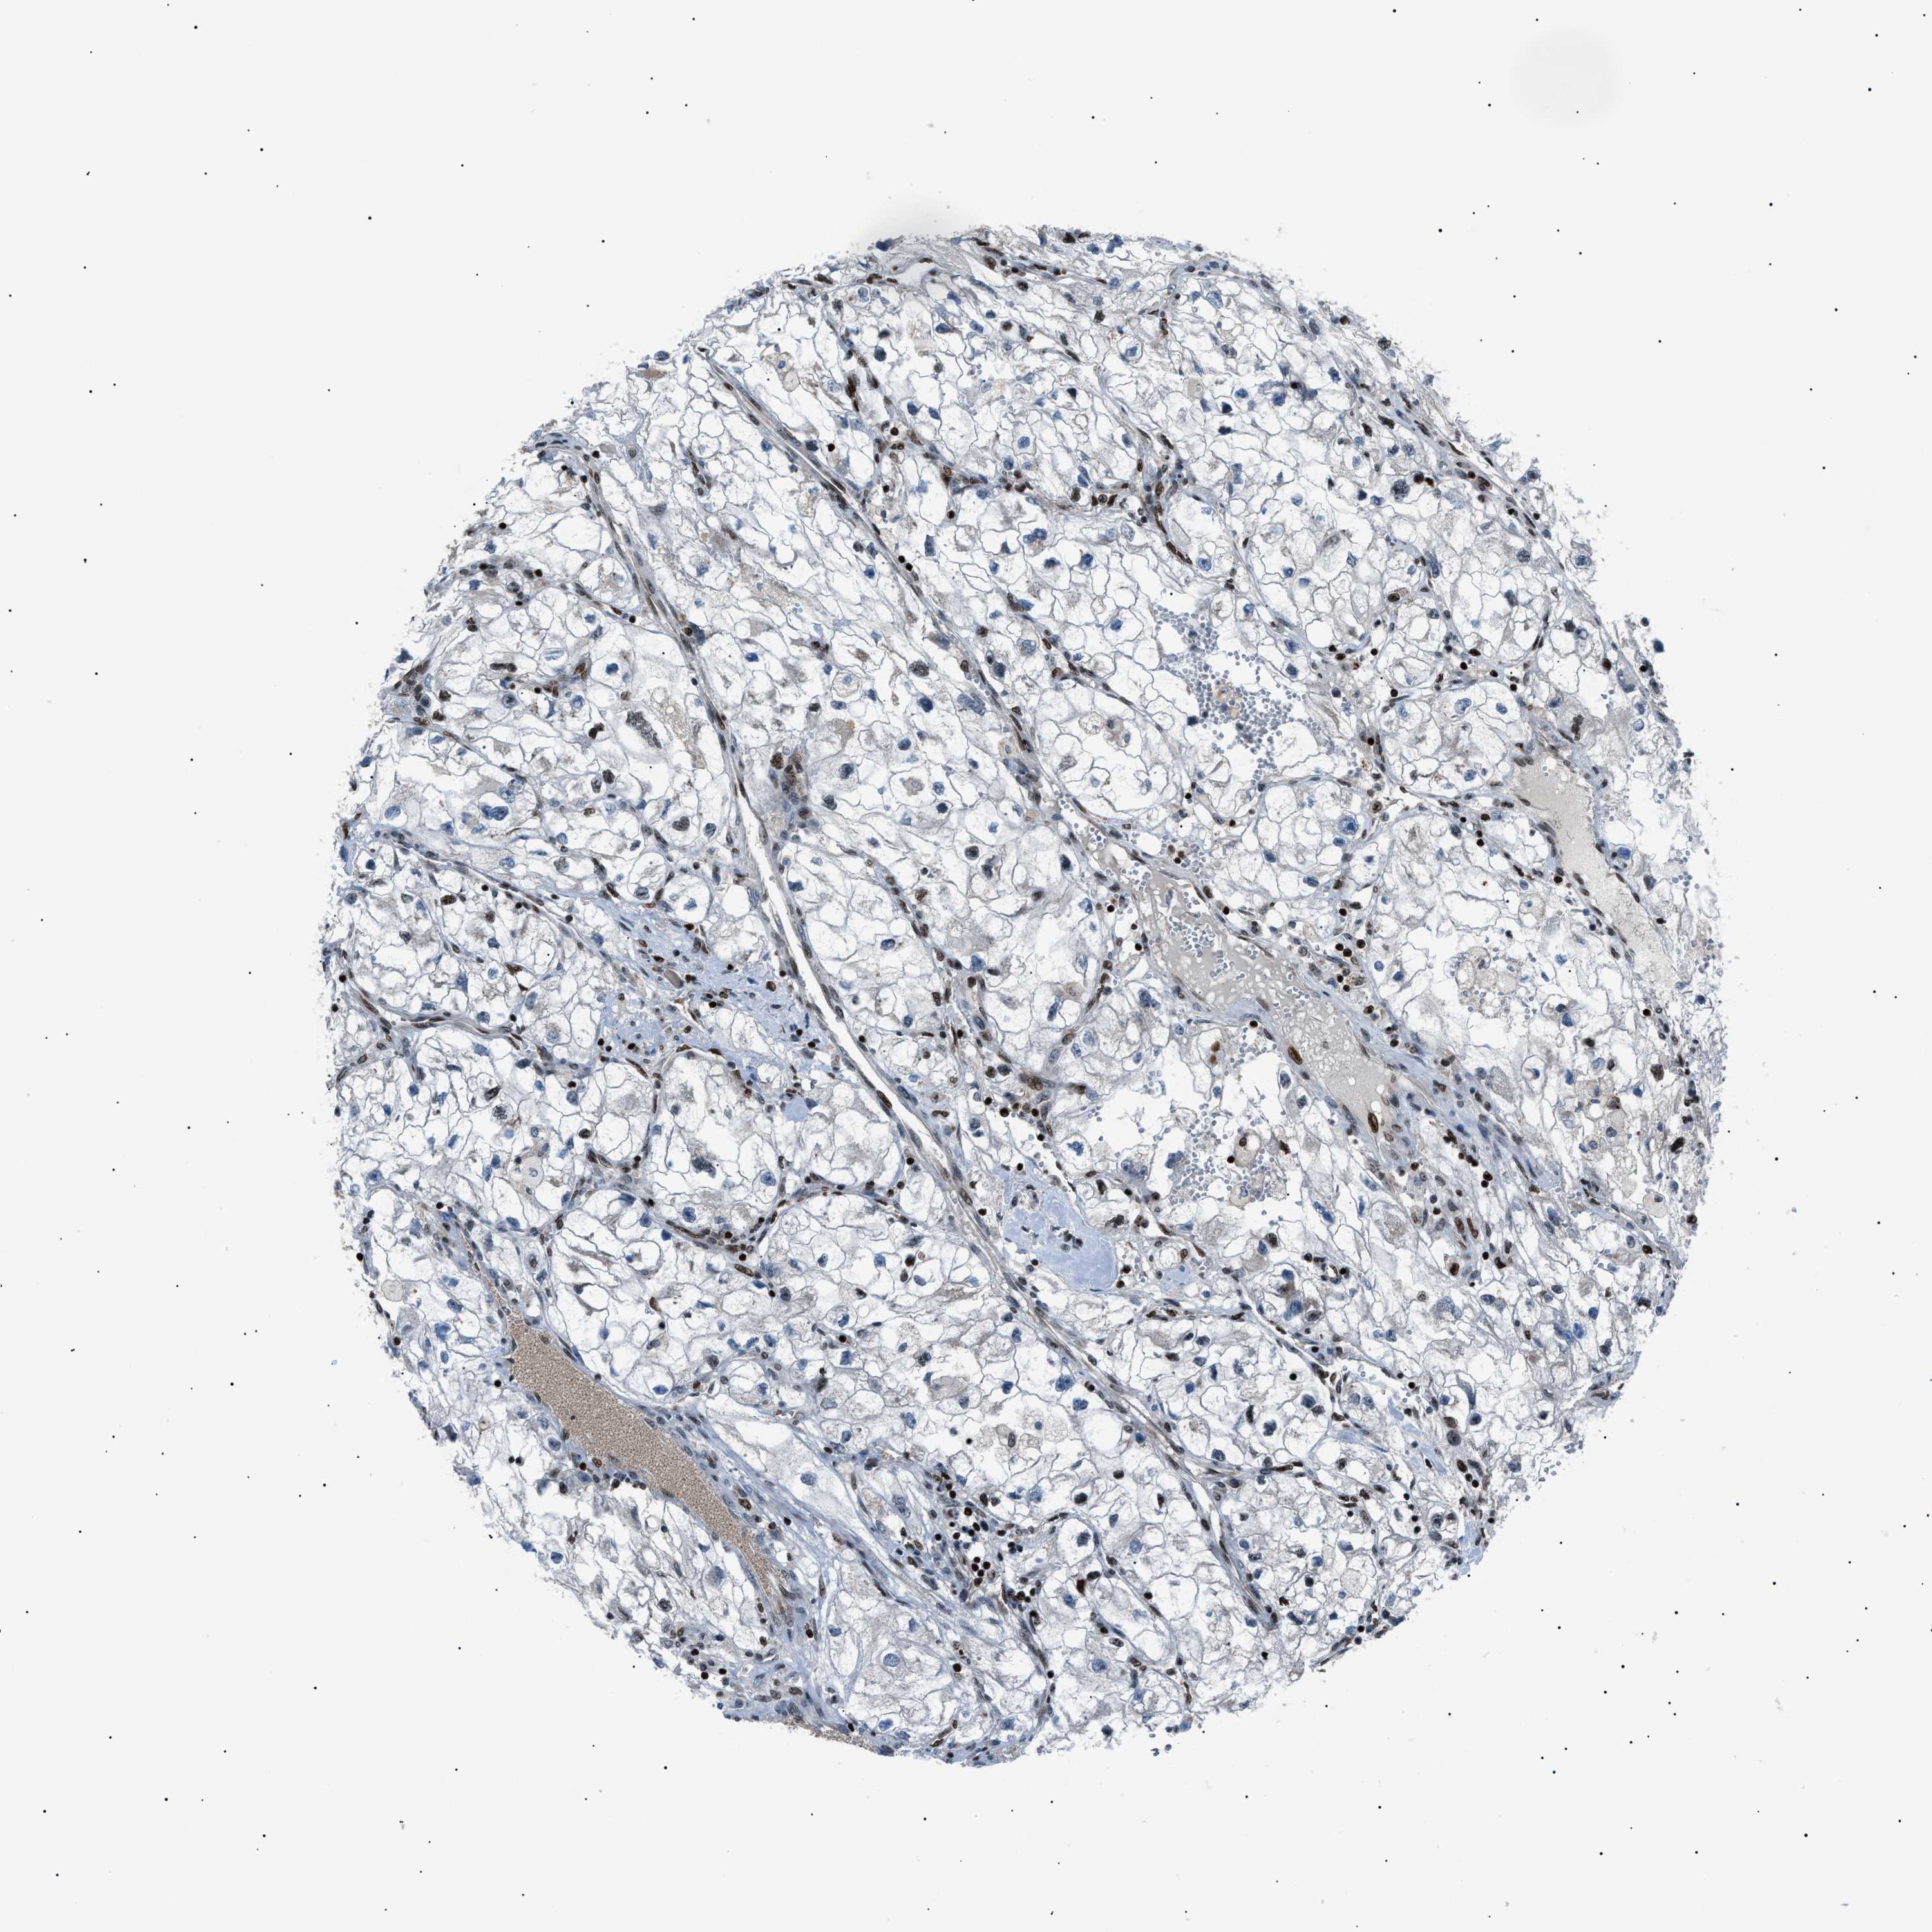

Kidney renal clear cell carcinoma

KIDNEY RENAL CLEAR CELL CARCINOMA (TCGA) - Interactive survival scatter ploti

The Survival Scatter plot shows the clinical status (i.e. dead or alive) for all individuals in the patient cohort, based on the same data that underlies the corresponding Kaplan-Meier plots. Patients that are alive at last time for follow-up are shown in blue and patients who have died during the study are shown in red.

The x-axis shows the expression levels (FPKM) of the investigated gene in the tumor tissue at the time of diagnosis. The y-axis shows the follow-up time after diagnosis (years). Both axes are complimented with kernel density curves demonstrating the data density over the axes. The top density plot shows the expression levels (FPKM) distribution among dead (red) and alive patients (blue). The right density plot shows the data density of the survived years of dead patients with high and low expression levels respectively, stratified using the cutoff indicated by the vertical dashed line through the Survival Scatter plot. This cutoff is automatically defined based on the FPKM cutoff that minimizes the p-score. The cutoff can be changed by dragging the vertical line or by entering a cutoff value in the square labeled "Current cut-off".

Under the Survival Scatter plot the p-score landscape (black curve; left axis) is shown together with dead median separation (red curve; right axis). Dead median separation is the difference in median mRNA expression between patients who have died with high and low expression, respectively. It is calculated as follows: median FPKM expression of dead patients with high expression - median FPKM expression of dead patients with low expression. This is intended to aid the user in visually exploring custom cutoffs and the associated p-scores and dead median separation.

Individual patient data is displayed and can be filtered by clicking on one or more of the category buttons on the top of the page. Categories describing expression level and patient information include: high, low, alive, dead, female, male and tumor stages. The scale of the x-axis can be toggled between linear and log-scale by clicking on the "x log" button. Mouse-over function shows TCGA ID, patient information and mRNA expression (FPKM) for each patient.

& Survival analysisi

Kaplan-Meier plots summarize results from analysis of correlation between mRNA expression level and patient survival. Patients were divided based on level of expression into one of the two groups "low" (under cut off) or "high" (over cut off). X-axis shows time for survival (years) and y-axis shows the probability of survival, where 1.0 corresponds to 100 percent.

PRKX is potential prognostic, high expression is favorable in Kidney Renal Clear Cell Carcinoma (TCGA)

Best expression cut offi

: 9.13

Average pTPM 9.3

Number of samples 521